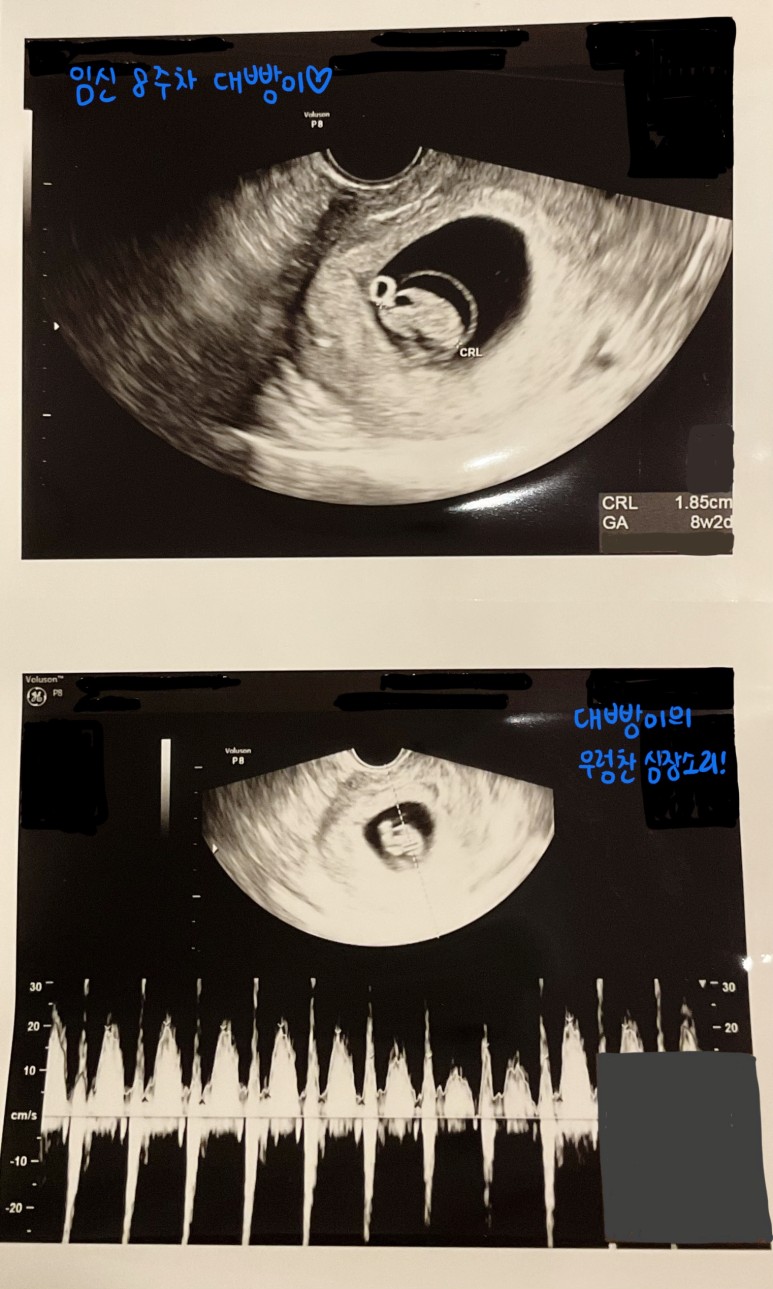

임신 8주차 병원 방문 시에는

다음과 같은 진료를 받았다.

② 머리~엉덩이 크기 확인

이번에 초음파 검사에서도

우렁찬 심장소리를 확인하고 -

2주 전에는 난황이 약간 커진 정도였는데

이번에는 조금 다른 모습!

4mm 였던 아기가

1.85 cm 가 되었다 ㅎㅎ